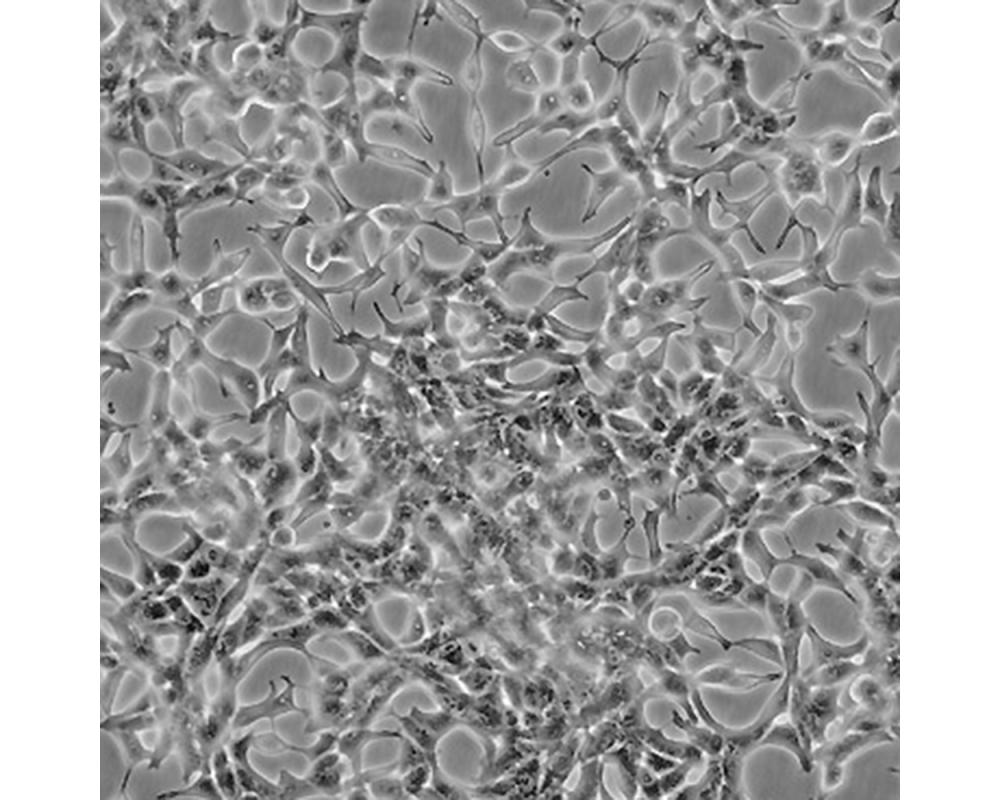

LNCaP clone FGC [LNCaP.FGC]

人前列腺癌細胞

前列腺癌;左鎖骨上淋巴結轉移;男性

形態特征

上皮細胞

生長特性

人前列腺癌細胞LNCaP克隆FGC是從一位50歲白人男性(血型B+)的左鎖骨淋巴結針刺活檢中分離,該患者經確診為前列腺癌轉移。 這株細胞對5-α-二氫睪酮(生長調節子和酸性磷酸脂酶產物)有響應。 這株細胞并不形成一致的單層,而是形成集落,在傳代時可以用滴管反復吹吸打碎。 它們僅僅輕輕地吸附在基底上,不形成匯合,很快使培養基變酸。 生長很慢。 傳代后48小時內不應擾動。 當培養瓶封包后,多數細胞從培養瓶底分離,懸浮在培養基中。 收到后,在通常培養單層細胞的條件下培養24到48小時,以合細胞再貼壁。